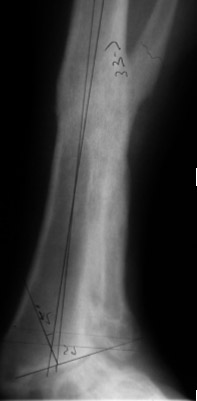

The surgeon in preparation for each surgery preconstructs a customized apparatus. Using wires or pins, the apparatus is surgically attached to the affected limb. Surgery is usually performed percutaneously through small incisions. Special care is taken to minimize injury to the bone and surrounding soft tissue, nerves and blood vessels when making specialized bone cuts.

During the adjustment phase the patient is followed up in the rooms every two weeks with clinical examination and x-rays. A close scrutiny is maintained to identify any complications early.

When the desired correction is achieved the frame is locked down and the consolidation phase begins. The patient is seen on a monthly basis with x-rays and examination.

I am very conservative regarding when to remove the frame. This is to minimize the risk of deformation of the regenerate or fracture after frame removal, which can be a devastating complication. When it is thought that it is time to remove the frame then it is completely loosened so that it is not assisting in weight bearing and the patient is encouraged to fully weight bear for two weeks. If this can be achieved without any loss of correction then the frame removal is scheduled. If there is loss of position then usually this can be corrected by frame adjustment on an outpatient basis thereby avoiding needing further surgery.